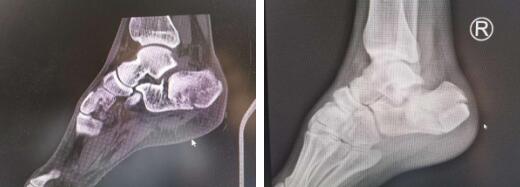

1.1右跟骨术前CT及X线

1.2右跟骨术前规划